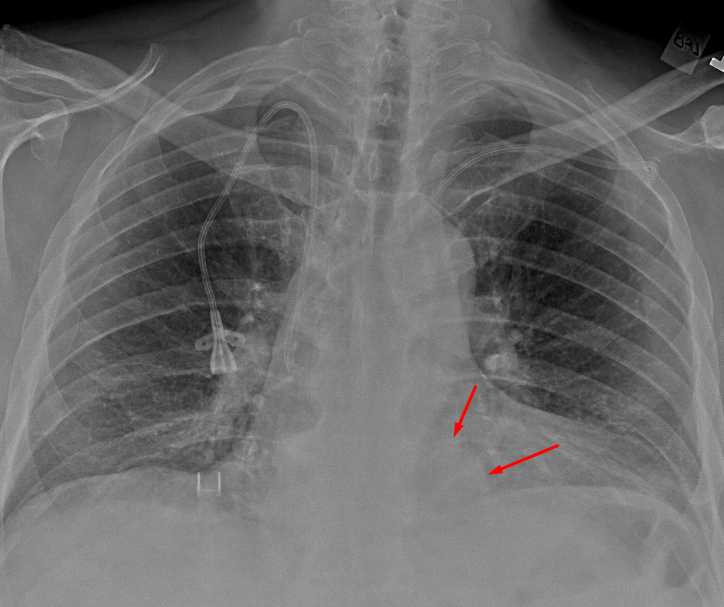

Age: 66

Sex: Male

Indication: Chest pain, fever

Sample ReportRounded opacity in the medial left lung base, which could represent a hiatal hernia or mass. Consider chest CT for further characterization.

Otherwise, no evidence of acute cardiopulmonary disease.